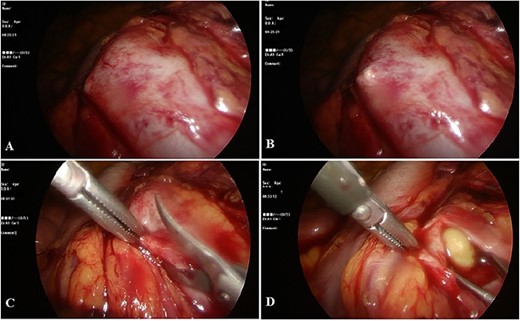

The procedure was conducted under general anesthesia, with the patient in the conventional lithotomy position. Utilizing a semirigid ureterorenoscope, the renal pelvis was accessed using a guide wire, allowing visualization of the stone. The access sheet was placed into the left ureter, followed by inserting an 8-Fr Foley catheter in the patient. The catheter is attached to the access sheet. The patient was repositioned in the lateral decubitus position. Following the establishment of sterile conditions, the peritoneum was accessed laterally to the rectus muscle using a Veress needle, and abdominal insufflation with CO2 was initiated. Then, a 10-gauge trocar was inserted through the lateral umbilicus, providing visualization of the intraperitoneal region. Additional 10-gauge and 5-gauge trocars were placed. Subsequently, the Toldt line underwent dissection. An access sheet was observed in the left ureter. By carefully tracing the course of the ureter, dissection was continued until it reached the left renal pelvis. The flexible ureterorenoscopy (f-URS) was inserted through the access sheet, allowing visualization of a stone within the left kidney. As shown in Fig. 2(A and B), the pelvic wall was identified using f-URS, and the marked area of the left renal pelvis, as indicated by f-URS, was incised using laparoscopic scissors (Fig. 2C). The stone was extracted using laparoscopic forceps (Fig. 2D). A guidewire was passed through the access sheet and advanced to the incision site. Subsequently, a 4.8-Fr, 24-cm double-J (DJ) stent was placed in the renal pelvis over the guidewire. Verification of the DJ catheter placement was performed using a scope. Under scope guidance, the access sheet was removed, and a two-way, 16-Fr catheter was replaced. The renal pelvis was meticulously sutured using a continuous 3.0 Vcyril suture technique. After the bleeding was controlled, a drain was placed in the lodge. The procedure was completed.

During operation: A and B: marking the location of the stone; C: opening of the renal pelvis with laparoscopic scissors; D: the process of removing stone.